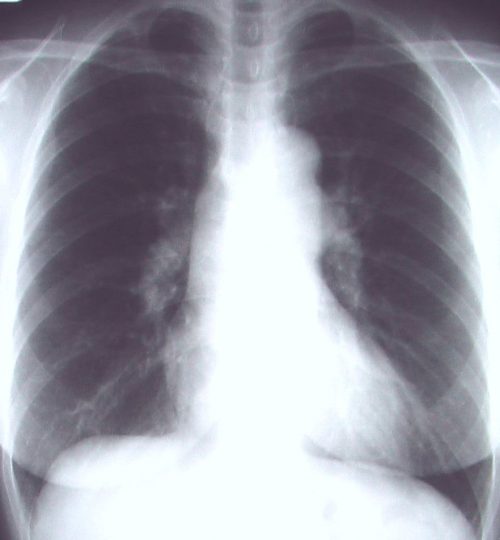

縦隔の拡大があり内部をみると血管陰影もしくは左房陰影の可能性があるが、右縁は大動脈弓に連続しており大動脈の蛇行(上行・胸部)と考えられる(横型心陰影にみられる正常バリエ-ション)右S3の結節影と縦隔の下部の不鮮明な所見には注意。

肺野の含気過多があり細気管支炎様のレントゲン像だが、同時に上縦隔右気管支上の部分が反対側の左と比べてやや白く透過性が悪くなっている。このような場合気管支S1もしくはS2の浸潤影初期のことがある。

5日後に確認したレントゲン像を下に提示する。